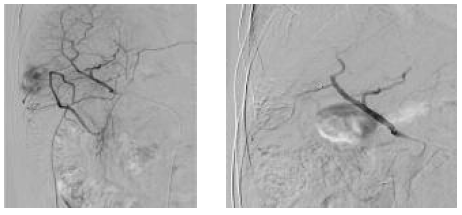

One such combined strategy is the combination of radiofrequency ablation and transarterial chemoembolization. A combination of transarterial chemoembolization followed by radiofrequency ablation has been used to minimize heat loss because of perfusion-mediated tissue cooling and to increase the therapeutic effect of radiofrequency ablation (Figures 5-9).26 Radiofrequency ablation and transarterial chemoembolization are more effective for complete tumor necrosis rate in patients with hepatocellular carcinoma.21,27 Local tumor progression rate was significantly lower in the transarterial chemoembolization and radiofrequency ablation-treated group than in the radiofrequency only ablation group (6%-39%).28

Figure 5 and 6. Hypervascular Hepatocellular Carcinoma Nodule in the Segment V of Liver, and Selective Embolization With Drug Eluting Bead-Transarterial Chemoembolization

Figure 7 and 8. Ultrasonography Visualization of Hepatocellular Carcinoma Nodule Before and After Selective Chemoembolization